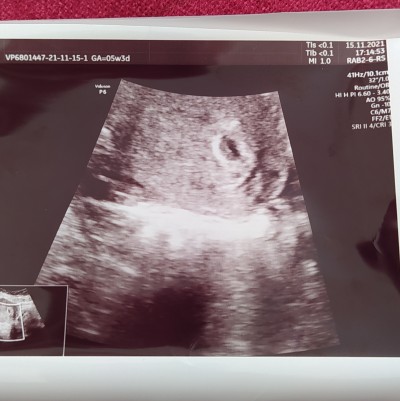

13 haftalık ultrason görüntüsü sizce kız mı erkek mi tahmini olan yazabilir misiniz

Kıza benziyor dedi doktor bildiniz☺️

Kıza benziyor dedi doktor

Göstermedi dedi bacak arasıni kapatmış

Çikolata yedim meyve suyu içtim ama malesef hemen arkasını döndü